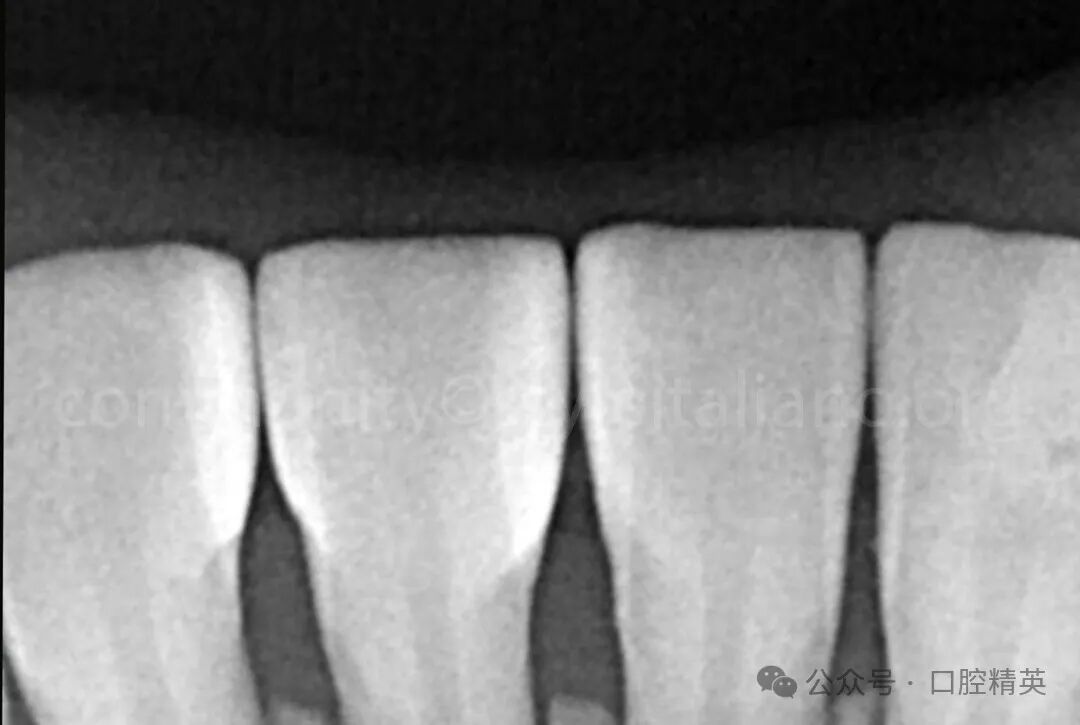

图9拍摄放射学图像以验证修复体的适合性,并确认无悬垂边缘。